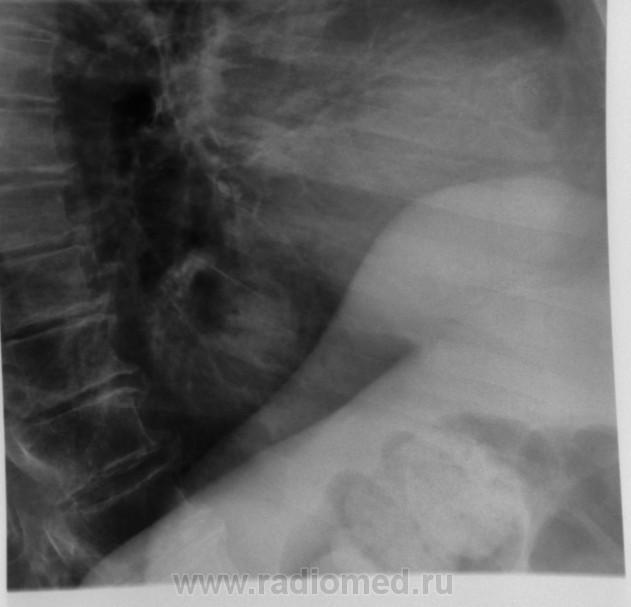

Ещё предложение: дать барий и исключить аксиальную грыжу.

yes. Частично внутригрудной желудок

Несомненно сочетание патологии.

К позвонкам стоит присмотреться

Ретроспективно зная, что это такое, ещё раз просматривая снимки , по боковой проекции  видно просветление  на фоне тени, с учётом  картины по прямой проекции, можно было бы и догадаться с чем имеем дело, но что-то не сработало в черепной коробке (видимо правльно говорят военные, что голова -это кость). Если серьёзно, такая картина нечасто встречается и как понимать термин-Частично внутригрудной желудок?Есть укорочение пищевода или пищевод нормальной длины ( тогда это будет фиксированная грыжа пищеводного отверстия диафрагмы).

Литический метастаз Th11.

Рак щитовидной железы. Диагноз верифицирован гистологически. Ответ биопсии получен вчера и из железы и из позвонка